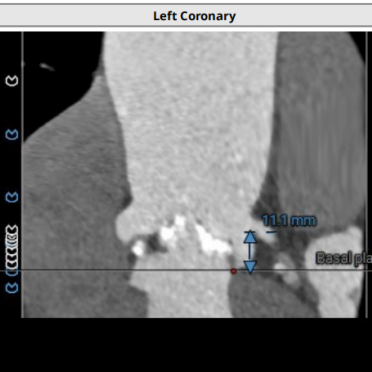

术前CT评估

● type1型二叶式主动脉瓣,L-R窦融合嵴,瓣叶明显增厚伴重度钙化;LVOT呈收口形;

● 左右冠脉开口高度尚可,切线位左右冠瓣叶长度>冠脉开口到瓣叶附着缘距离;